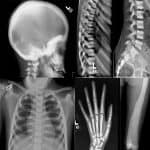

Bệnh Albers – Schonberg hay còn gọi là bệnh xương hóa đá (Osteopetrosis) là bệnh lý bẩm sinh hiếm gặp do mất khả năng hấp thụ xương của các huỷ cốt bào, do đó quá trình tái tạo xương bị tổn thương. Tỷ lệ mắc bệnh ước tính là 1/100.000-500.000 dân. Xương trở lên cứng và dày, nhưng cấu trúc bất thường của chúng thực sự khiến chúng yếu và giòn…